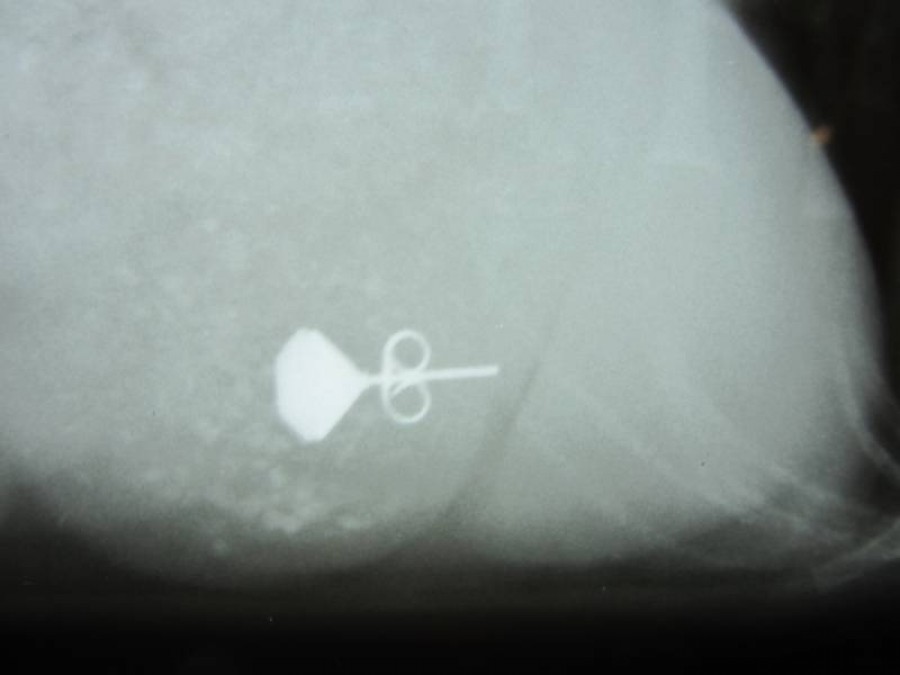

A képeken látható a fülbevaló röntgenképe, a fülbevaló eltávolítás után és a kutyus a varratszedéskor.

Miután nem jött ki természetes módon, így műtéti úton távolítottuk el. Szerencsére a műtét után a kutyus gyorsan és szövődménymentesen épült fel. A gazdi már büszkén hordhatja a „madárlátta” fülbevalót.